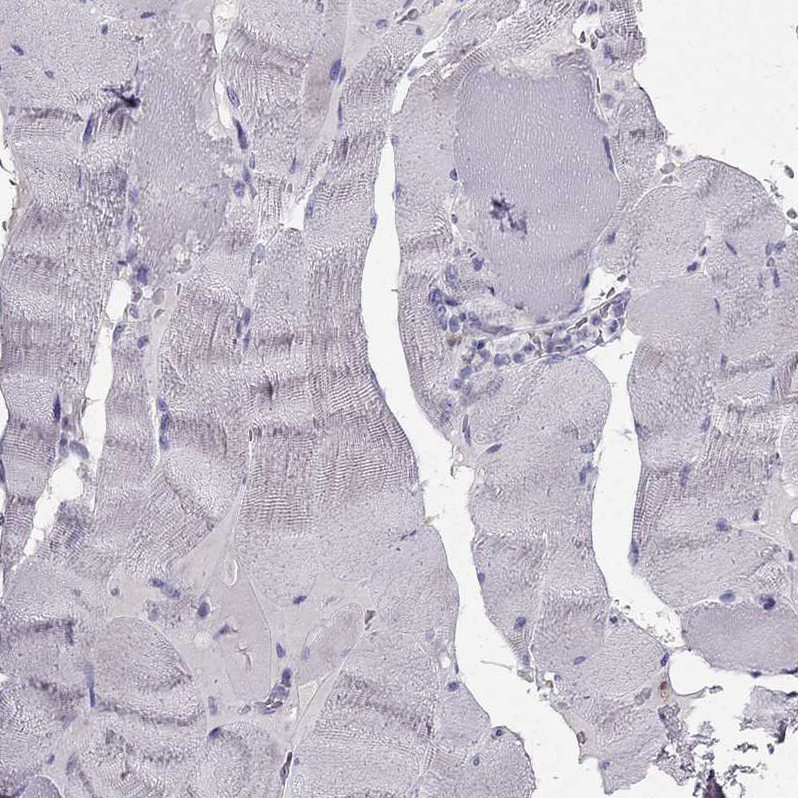

Immunohistochemical staining of human cerebral cortex shows strong granular cytoplasmic positivity in neurons and neuropil.